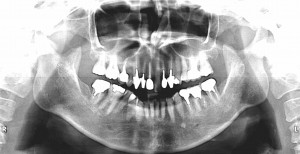

症例⑤

上左右の奥歯を失ってしまったため、保険の入れ歯を入れたが、違和感が強く、しっかり噛むことができないため、インプラントを併用した入れ歯を作ることで違和感なく、しっかり噛むことができるようになった。 また通常の入れ歯は、はずれないようにするため金属のバネを歯に引っ掛けるため見た目も悪いが、インプラントによって固定されているためバネもなく、見た目も非常に良いものとなっている。

術前

術前レントゲン写真

術後レントゲン写真